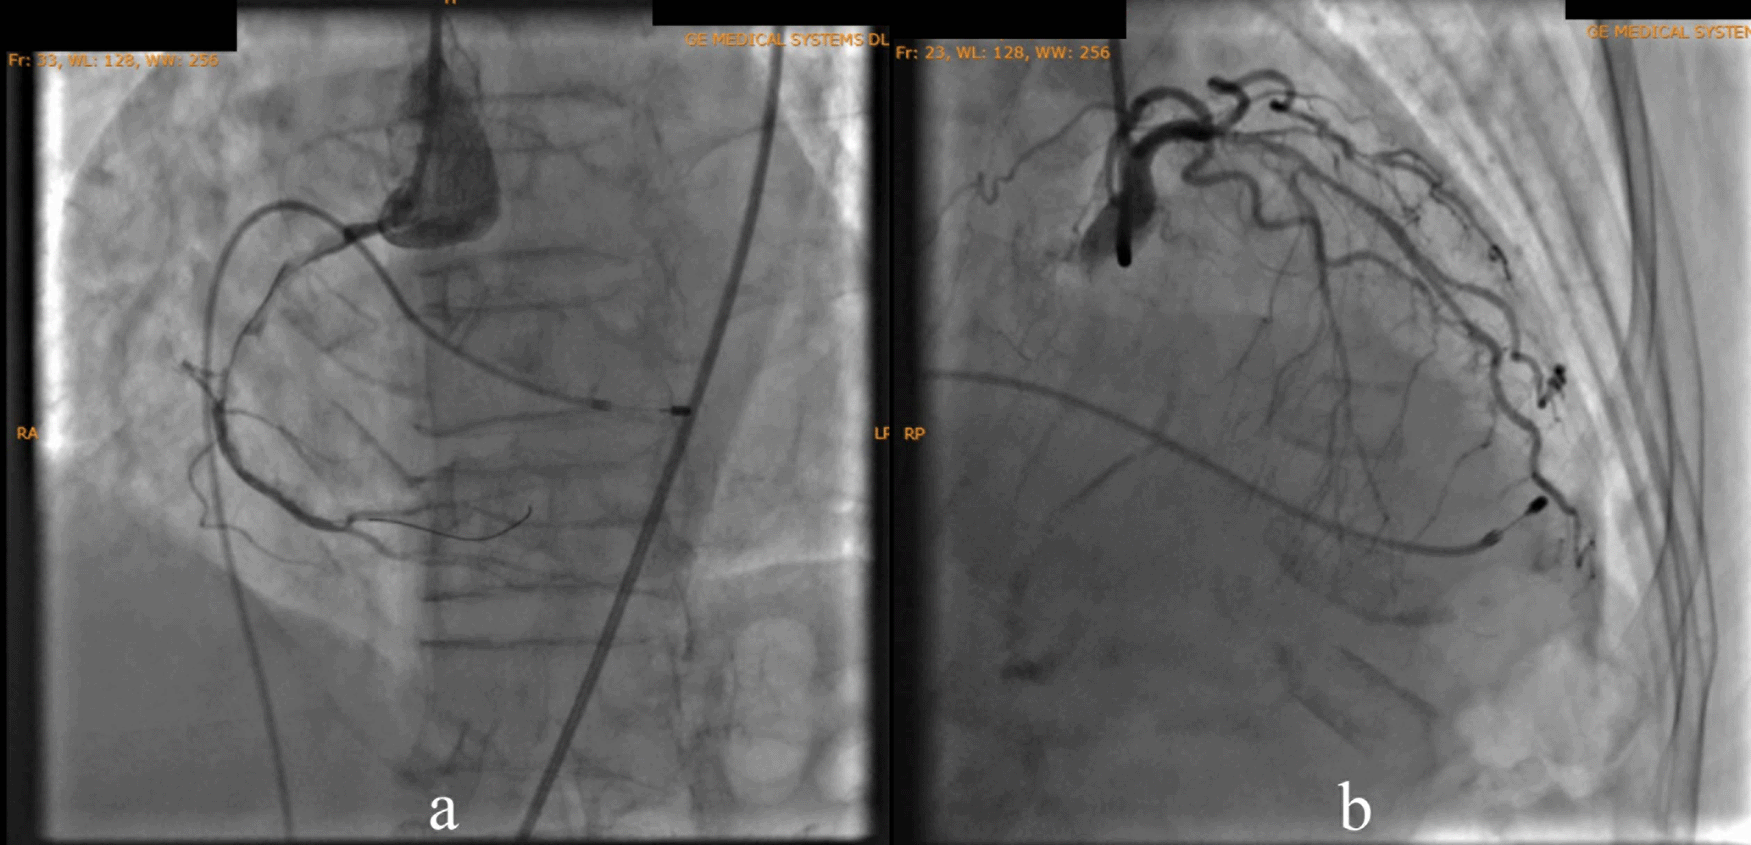

According to the DCA, the total occlusion was at the proximal right coronary artery (RCA) (Figure 2). There was insignificant stenosis in the proximal-mid left anterior descending artery. Besides, there were no stenosis on the left circumflex artery and the left main coronary artery. Primary PCI at the RCA was conducted using drug eluting stent (DES) promus and then thrombolysis in myocardial infarction (TIMI) grade 3 flow was shown at the RCA (Figure 3). Electrocardiography was also conducted after the installation of the pacemaker (Figure 4).